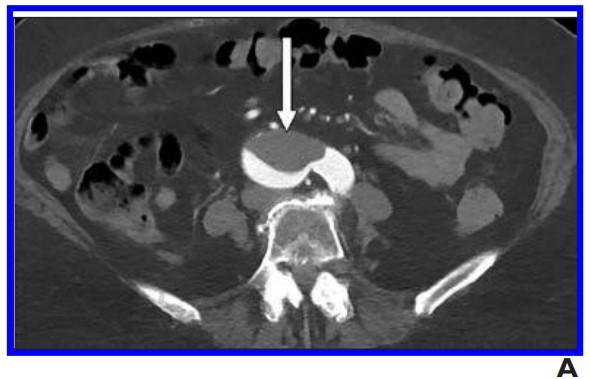

image: A, 76-year-old woman who presented to emergency department with upper back pain. Axial abdominopelvic CT angiogram shows nonocclusive acute aortic thrombus (arrow). Bilateral common iliac artery and left internal iliac artery thrombi (not shown) were also seen, as well as signs of chronic atherosclerotic disease. After findings of concurrently performed chest CT raised concerns, patient was determined to have COVID-19.

Nine (11%) patients with COVID-19 had thromboembolic findings (seven men, two women; mean age 67.0). Thromboembolism was described in four of the 38 CT reports (10.5%). Two others described splenic infarctions with patent vasculature (overall positivity rate, 15.8% [6/38]). Three patients had arterial thromboembolism in the aorta or major branches.